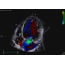

The 4D ICE NUVISION Catheter offers real-time volumetric imaging, a 90x90 field of view, 4D color Doppler flow capabilities, and an independently rotating tip, making it an ideal choice for left atrial appendage closure (LAAC) procedures.